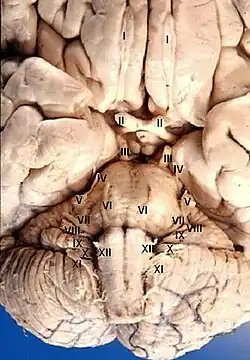

The cranial nerves emerge from the central nervous system above the level of the first vertebra of the vertebral column.[2] Each cranial nerve is paired and is present on both sides. There are conventionally twelve pairs of cranial nerves, which are described with Roman numerals I–XII. Some considered there to be thirteen pairs of cranial nerves, including cranial nerve zero. The numbering of the cranial nerves is based on the order in which they emerge from the brain and brainstem, from front to back.[2]

Most typically, humans are considered to have twelve pairs of cranial nerves (I–XII), with the terminal nerve (0) more recently canonized.[2][5] The nerves are: the olfactory nerve (I), the optic nerve (II), oculomotor nerve (III), trochlear nerve (IV), trigeminal nerve (V), abducens nerve (VI), facial nerve (VII), vestibulocochlear nerve (VIII), glossopharyngeal nerve (IX), vagus nerve (X), accessory nerve (XI), and the hypoglossal nerve (XII).

Cranial nerves are numbered based on their position from front to back (rostral-caudal) of their position on the brain,[8] as, when viewing the forebrain and brainstem from below, they are often visible in their numeric order. For example, the olfactory nerves (I) and optic nerves (II) arise from the base of the forebrain, and the other nerves, III to XII, arise from the brainstem.[8]

Exiting the brainstem

With the exception of the olfactory nerve (I) and optic nerve (II), the cranial nerves emerge from the brainstem. The oculomotor nerve (III) and trochlear nerve (IV) emerge from the midbrain, the trigeminal (V), abducens (VI), facial (VII) and vestibulocochlear (VIII) from the pons, and the glossopharyngeal (IX), vagus (X), accessory (XI) and hypoglossal (XII) emerge from the medulla.[12]

The olfactory nerve (I) and optic nerve (II) emerge separately. The olfactory nerves emerge from the olfactory bulbs on either side of the crista galli, a bony projection below the frontal lobe, and the optic nerves (II) emerge from the lateral colliculus, swellings on either side of the temporal lobes of the brain.[12]